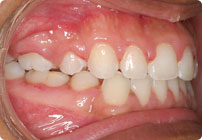

Antes

Caso: 11 años

Adolescente: Clase II

Mordida Cruzada Posterior

Sin extracción

Sin uso de expansores

6 alambres superiores

5 alambres inferiores

Sin uso de elásticos

Retenedores: Interior Fijo de TMA y Hawley en superior

Tiempo de tratamiento: 14 Visitas